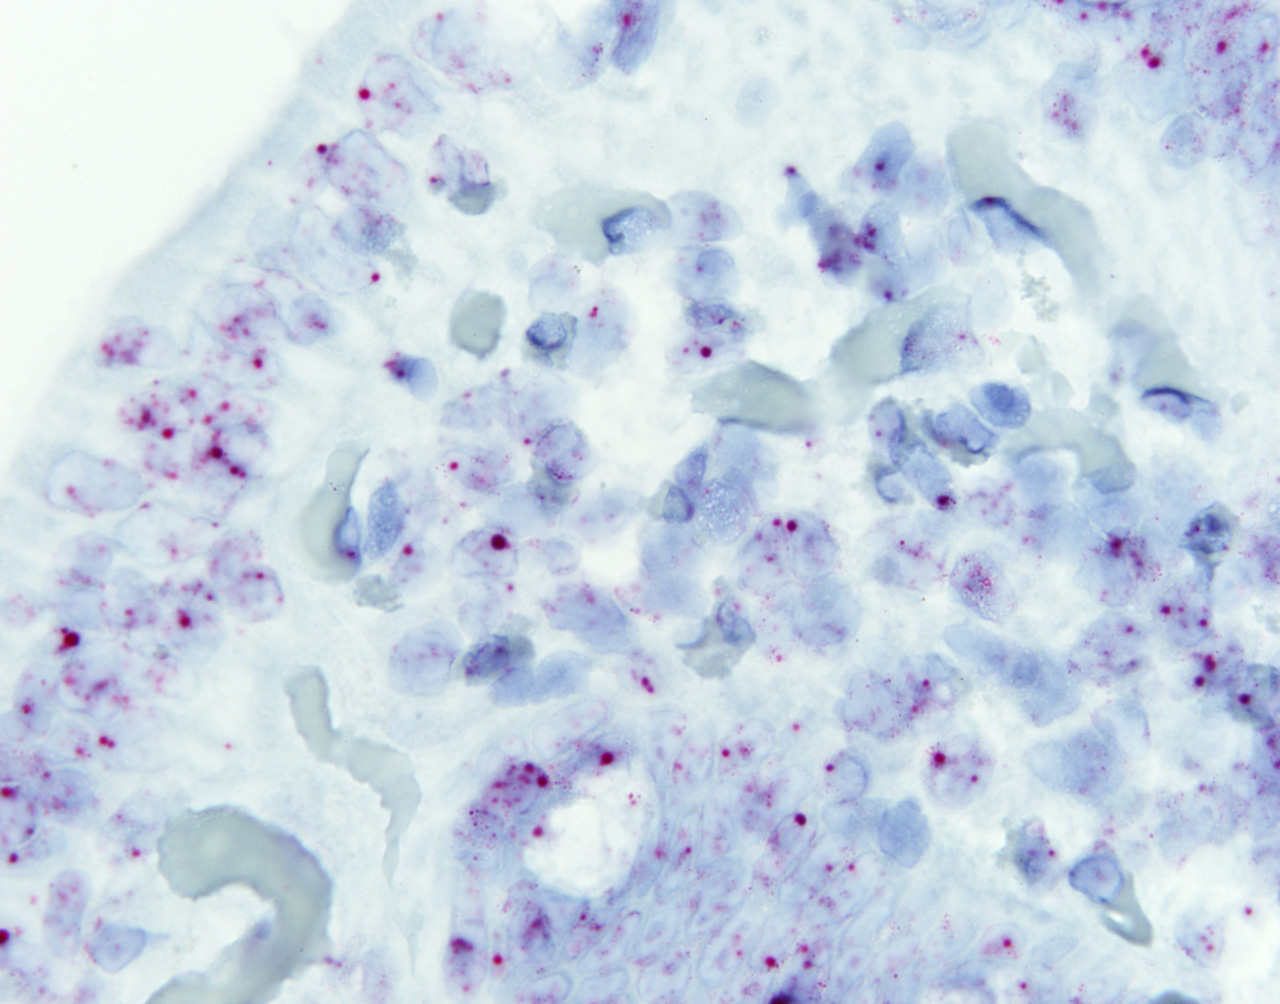

En una de estas regiones del genoma basura, han encontrado un gen clave en la regulación de la respuesta inflamatoria observada en los pacientes celíacos: es el lnc13. El ácido ribonucleico que produce ese gen pertenece a la familia de los ARN largos no codificantes (long non-coding RNA o lncRNA, en sus siglas en inglés) y se encarga de mantener los niveles normales de expresión de genes proinflamatorios. En las personas celíacas, este ARN no codificante apenas se produce, con lo que no se regulan adecuadamente los niveles de estos genes inflamatorios, que incrementan su expresión. Pero además de producirse en cantidades bajas, el lnc13 que producen los pacientes celiacos presenta una variante que altera su funcionamiento. "De esta forma se crea un ambiente inflamatorio que propicia el desarrollo de la enfermedad", indica Ainara Castellanos.